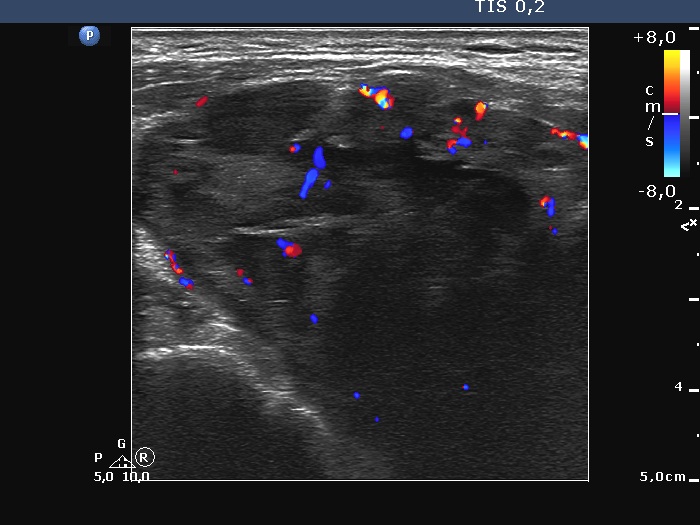

Ultrasonography. The right lobe was extremely enlarged with the dimensions of 50, 50 and 85 mm, depth, width and length, respectively. This lobe was composed of multiple hypoechoic areas within an echonormal background. The left lobe also had a hypoechoic lesion.